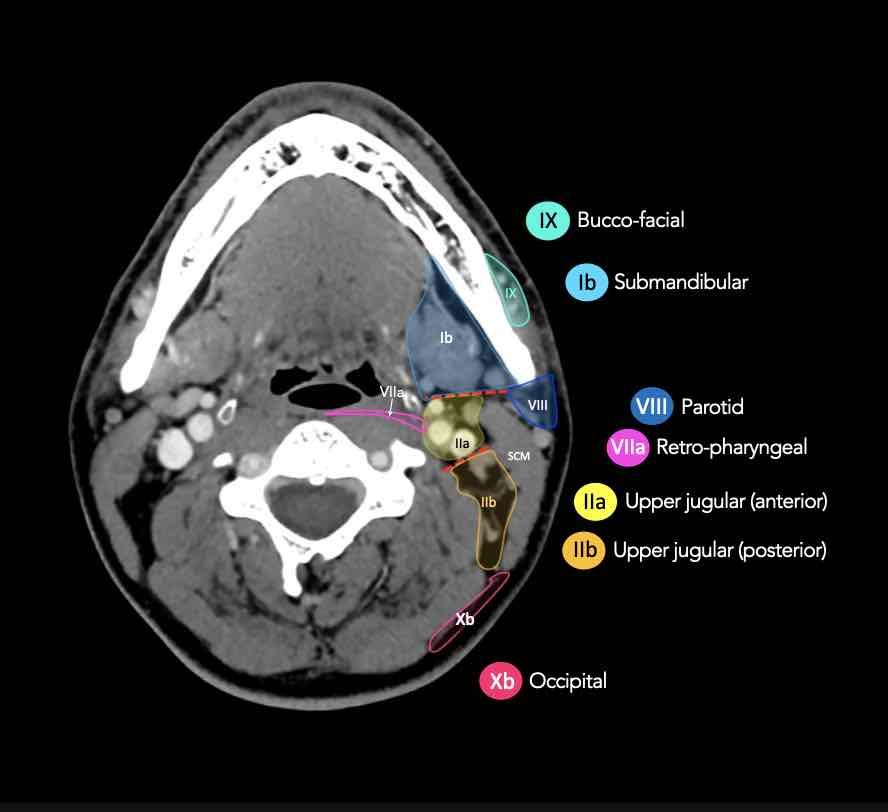

CT Scan Mặt Cắt Ngang (Axial CT)

Các lát cắt CT mặt phẳng ngang tương ứng với hình minh họa tổng quan.

Các lát cắt CT mặt phẳng ngang với hình ảnh chi tiết hơn.

Nhấp vào hình ảnh để phóng to.

Tầng II có thể được chia thành tầng IIa và tầng IIb bằng cách vẽ một đường tại bờ sau của tĩnh mạch cảnh trong.

Các hạch bạch huyết ở tầng IIa và IIb có nguy cơ chứa di căn từ các ung thư hốc mũi và khoang miệng, vòm hầu, hầu miệng, hạ hầu, thanh quản và các tuyến nước bọt lớn.

Tầng IIb thường liên quan hơn đến các khối u nguyên phát ở hầu miệng hoặc vòm hầu, và ít thường xuyên hơn với các khối u ở khoang miệng, thanh quản hoặc hạ hầu [1].